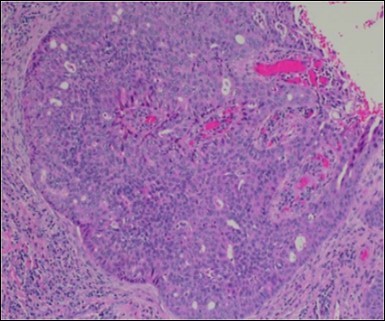

Granular arrangement of malignant cells and intercellular bridges are conspicuous with the demonstration of nuclear atypia, pleomorphism, prominent mitosis and tumour necrosis. A peripheral palisade is discernible within the cellular aggregates. Mitotic figures are common and can be quantified as up to 12 mitosis/ high power field. Tumour differentiation can prominently be of the ductal category with the demonstration of intra-cytoplasmic lumina. Comedo type tumour necrosis is evident along with foci of squamous differentiation The neoplasm is reactive to periodic acid Schiff ‘s (PAS) stain. (Figure 1, Figure 2, Figure 3, Figure 4, Figure 5, Figure 6, Figure 7, Figure 8, Figure 9, Figure 10, Figure 11, Figure 12, Figure 13.

Figure 1.Solid aggregates of tumour cells and duct structures in eccrine porocarcinoma (14).